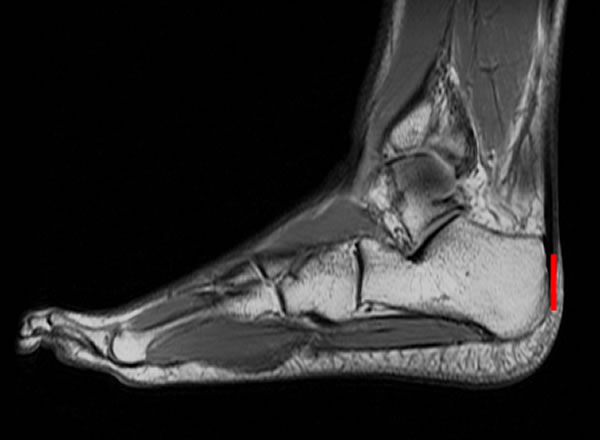

长跑运动员的脚部核磁共振图,跟骨与跟腱紧密连接,测量跟骨的长度(红线)有助于研究者确定长跑能力。

研究者选择了一些长跑运动员来进行测验,运动员在跑步机上以10英里/小时的速度跑10分钟,而研究者则记录下运动员的耗氧率、跟骨与踝骨的图像。结果显示,跟骨与踝骨越是短而平,氧气的使用率越高。对13块来自30000-20000年前的古人类跟骨化石及其同时期的6块尼安德特人跟骨化石的测量结果显示,古人在奔跑时耗费的能量比现代运动员约多6.9%,而尼安德特人则多出11.4%。研究者补充说,虽然解剖学上的特质比起专业训练来讲对奔跑的影响大得多,但是他们在研究过程中还是排除了训练的影响因素以期得到更准确的结果。(神秘的地球www.uux.cn)